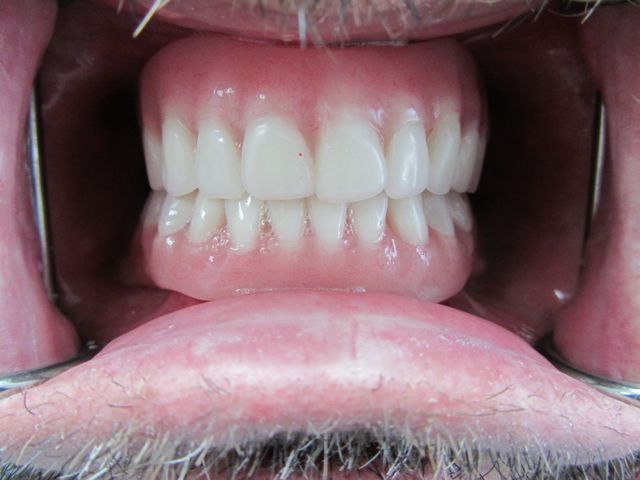

Photo from the side showing how the upper and lower teeth engage. Everything looks ideal.

If you look real closely, you can see that tooth No. 9 has dropped a bit. I know during denture fabrication that teeth can shift in the final stages. Some of our patients like having teeth that are set irregularly because they look more like “normal” teeth, and some patients would prefer that they be set to optimal perfection. If Mike prefers, I can take a sanding disk and polish No. 9 to make the two central teeth perfectly symmetrical.